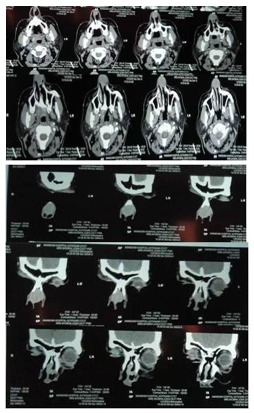

Computed tomography of the Nose-PNS showed a well-defined homogeneous mass lesion in the anterior nasal cavity along the anterior 1/3rd of nasal septum cartilaginous portion measuring approximately 2.5x2.4cm in size. There were no signs of bone destruction (Figure no 2a, 2b).

Figure 2a, 2b: Axial and coronal section of CT nose-PNS. Homogenous mass seen in anterior part of nasal cavity involving nasal septum.